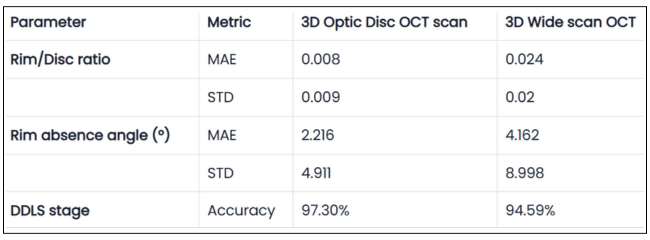

Altris AI’s survey identified a lack of data and increased patient wait times as the top problems with referrals for practitioners, while lack of co-management tools and poor communication/feedback ranked lower.

Let’s dive into more details:

Optometry referral: top problems